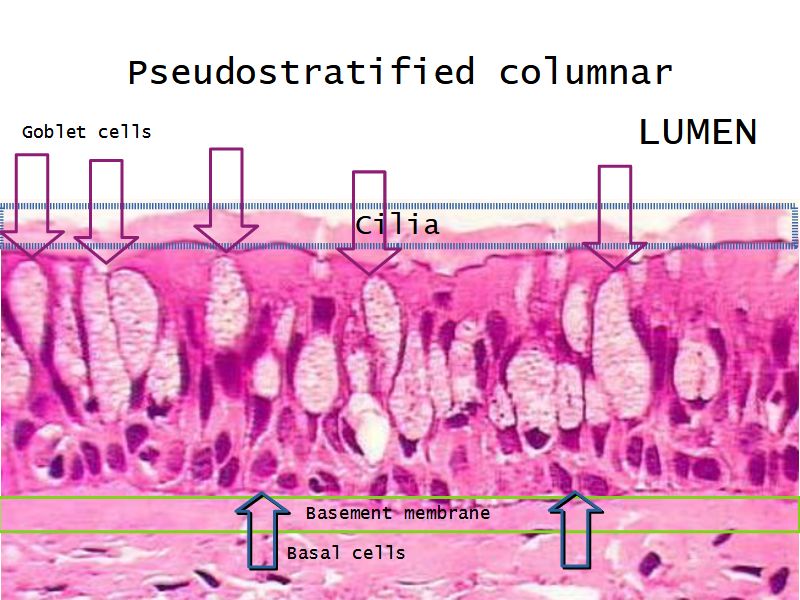

Respiratory epithelium

- Pseudostratified

- Ciliated

- Columnar

- Epithelium with

- 4 Cells

- Ciliated columnar cells

- Non-ciliated columnar cells

- Goblet cells

- Basal cells